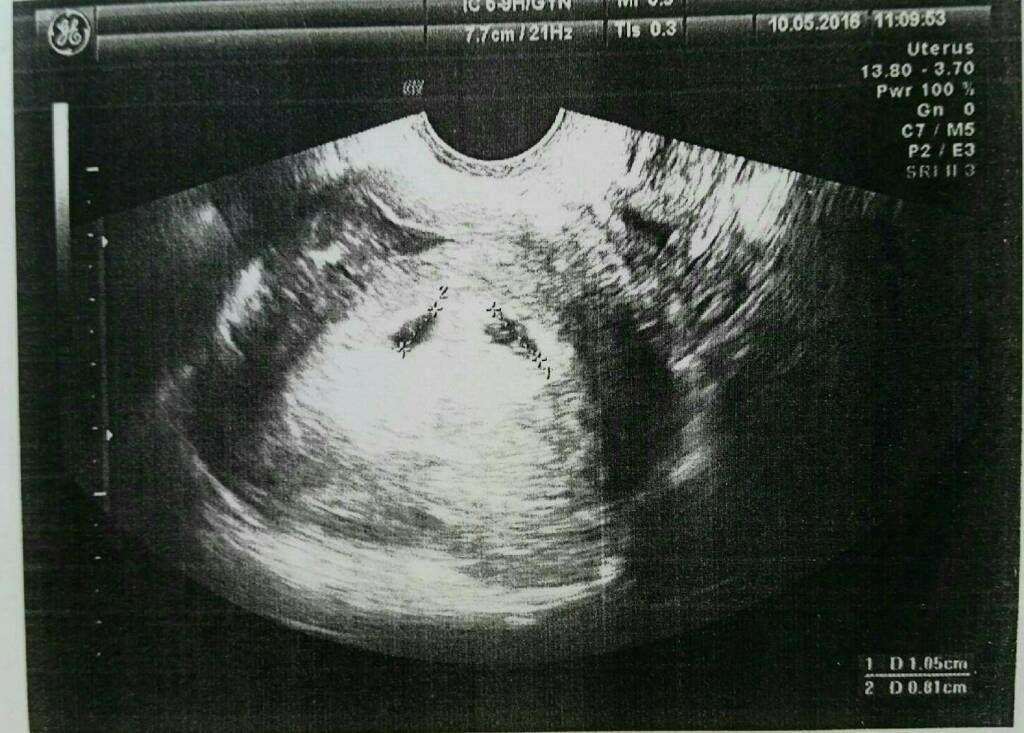

Moje pęcherzyki też były tak blisko siebie ułożone cieszysz się czy jesteś przerażona?

To moje bąbelki :-) troszkę większe niż twoje :-)